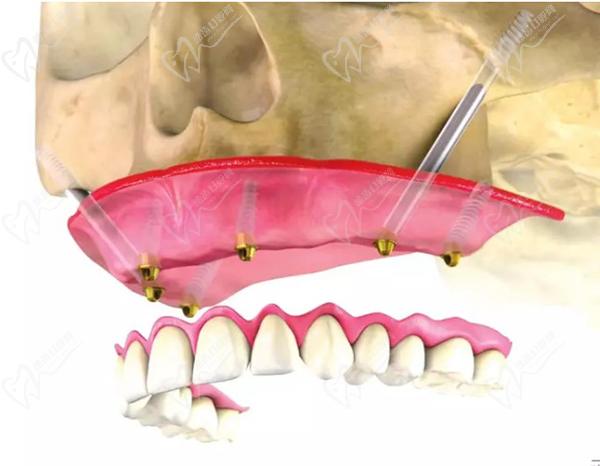

穿顴種植手術(shù),是通過將兩顆超長(zhǎng)植體斜植入顴骨來獲得超高的固位成效,然后在前牙區(qū)在垂直植入2-3顆普通植體,對(duì)于頜骨吸收情況比較重的牙友可以使用四顆穿顴種植體。穩(wěn)定性非常強(qiáng),是即刻種植修復(fù)技術(shù),大大縮短了種植牙時(shí)間,避免了大量植骨帶來的愈合等待期和風(fēng)險(xiǎn)。

穿顴種植牙示意圖:

穿顴種植牙示意圖